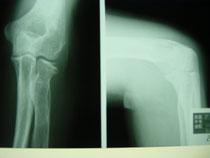

●右鎖骨骨折

当患者さんは手術療法に強く抵抗があり当院での保存療法を選択されました。

骨折部位の短縮転移があたので整復操作が必須になります。運よく短縮転移が矯正されたので保存療法で経過をみました。暑い時期だったので来院の度に固定を外し体を清拭して施術後、新しい下着の上から再度固定をする運びになりました。

骨折部位には超音波、患部以外の所は関節運動、経過を見て軽いマッサージを開始。固定も少しずつ簡易な物へ変更し二カ月後には三角巾のみ、三ヵ月経過すると肩関節の挙上もできるようになりました。

経過良好で完治しました。

左のレントゲンは短縮転位 (受傷時) 右は整復操作をして骨片が重なり合っている状態

整復後包帯と装具で固定。当初は週に2、3回来院してもらいその都度固定は取り外し、体を洗いました。

通常整形外科では取り外しも清拭もしないので暑い時期は患者様には試練です。ストレスは悪影響をもたらします。

局所には超音波治療を施し浮腫みのある指、肘はマサージににより軽減に努めました。6週ほど固定しましたが、各週ごとに固定を楽にしていくのでかなりストレスを軽減できたと思います。3か月目には肩を挙上できるまでになり、筋力強化運動により完治しました。